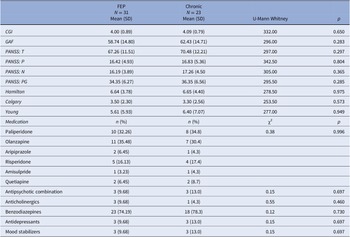

The patients’ sociodemographic data are shown in Table 1. There were significant differences in age (0.04), work status (0.032), and coexistence (0.001) between the FEP and chronic groups (0.04).

Table 1. Sociodemographic characteristics of subjects.

Abbreviation: FEP, first-episode psychosis.

* Tukey HSD (p < 0.05): Control ≠ Chronic patients; FEP ≠ Chronic patients.

The final sample consisted of 85 subjects, which included 31 FEP patients with nonaffective psychotic disorders (a manic episode with psychotic features, schizoaffective disorder, transient psychotic disorders, persistent delusional disorder, bipolar affective disorder with psychotic features, and schizophreniform disorder), 23 chronic patients with schizophrenia and persistent auditory hallucinations, and 31 HCs.

Psychopathological measurements

Patients were assessed by personnel trained in FEP evaluation. Interviews were conducted during the first episode and a few days after the start of treatment (JS). All FEP patients underwent several psychopathological measurements, including the Clinical Global Impression [Reference Haro, Kamath, Ochoa, Novick, Rele, Fargas, Rodríguez, Rele, Orta, Kharbeng, Araya, Gervin, Alonso, Mavreas, Lavrentzou, Liontos, Gregor and Jones20], to provide a global rating of illness severity, improvement, and response to treatment; the Global Assessment of Function [Reference Jones, Thornicroft, Coffey and Dunn21], to provide understanding about how well FEP patients could perform everyday activities; and the PANSS [Reference Kay and Opler22], which is a well-established scale that has been used to assess schizophrenia symptoms objectively. The results of the clinical measurements are summarized in Table 2. No significant clinical differences were found in any of these scales between the FEP and chronic groups.

Table 2. Clinical characteristics of subjects.

Abbreviations: CGI, Clinical Global Impression; GAF, Global Assessment of Function.